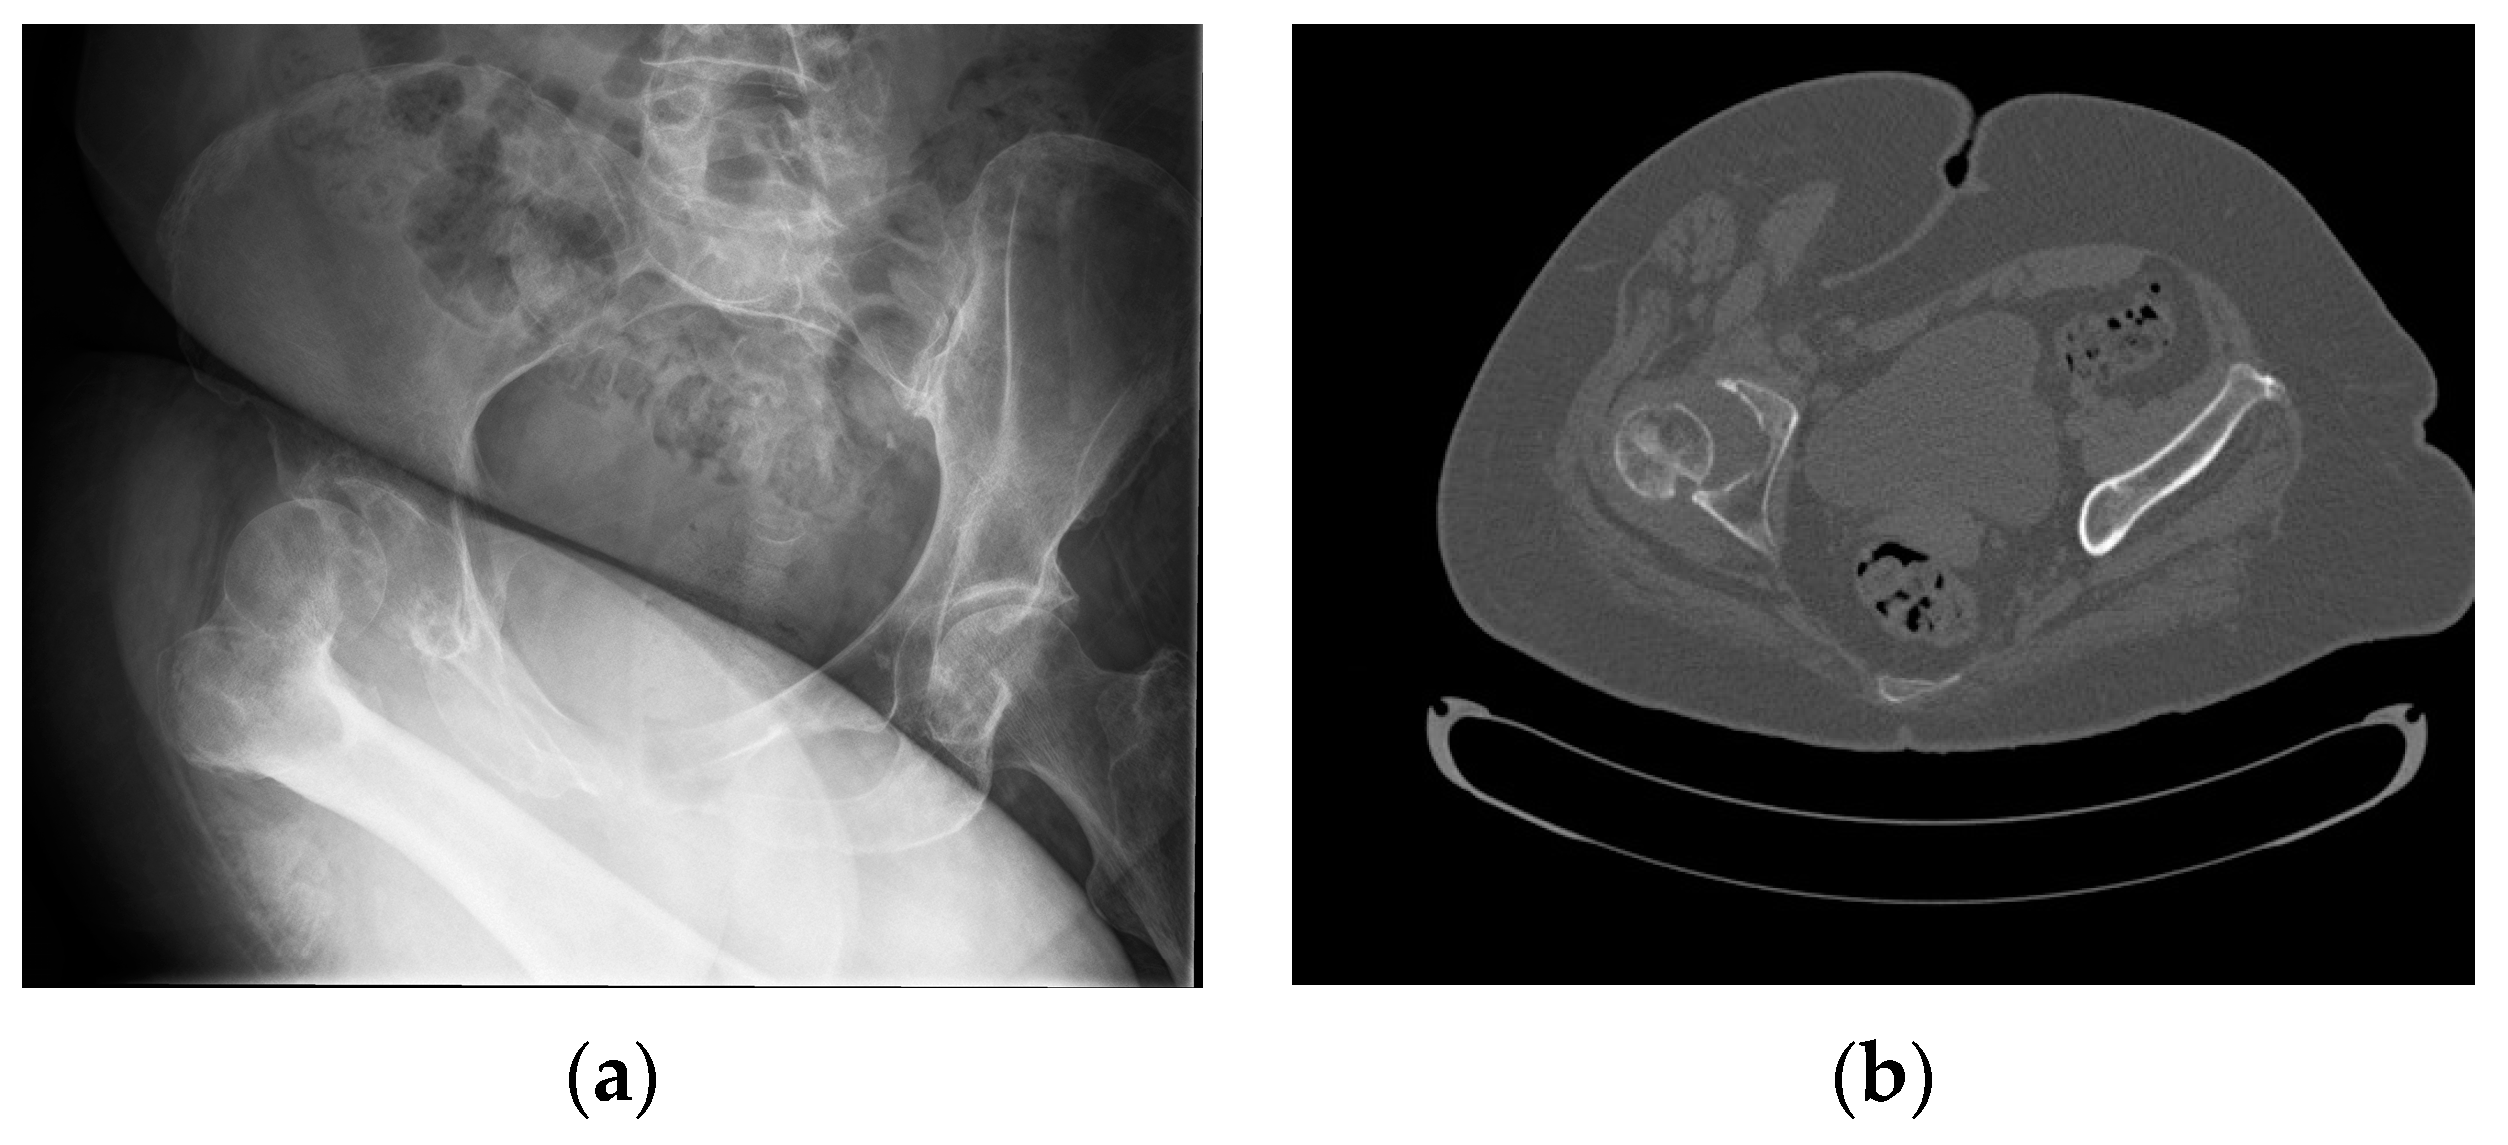

2. Case Presentation

2.1. Two-Stage Open Reduction